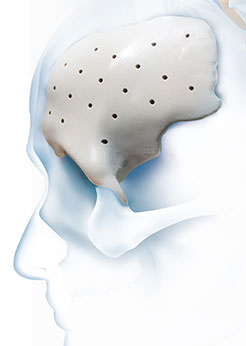

医療機具の輸入

主に医療機器、特にインプラント技術の研究開発、製造、販売を行っています。3Dプリンティング技術や生体材料を活用した医療分野での革新を追求し、特に骨科、神経外科、整形外科などの分野で高性能のインプラントやデバイスを提供しています。